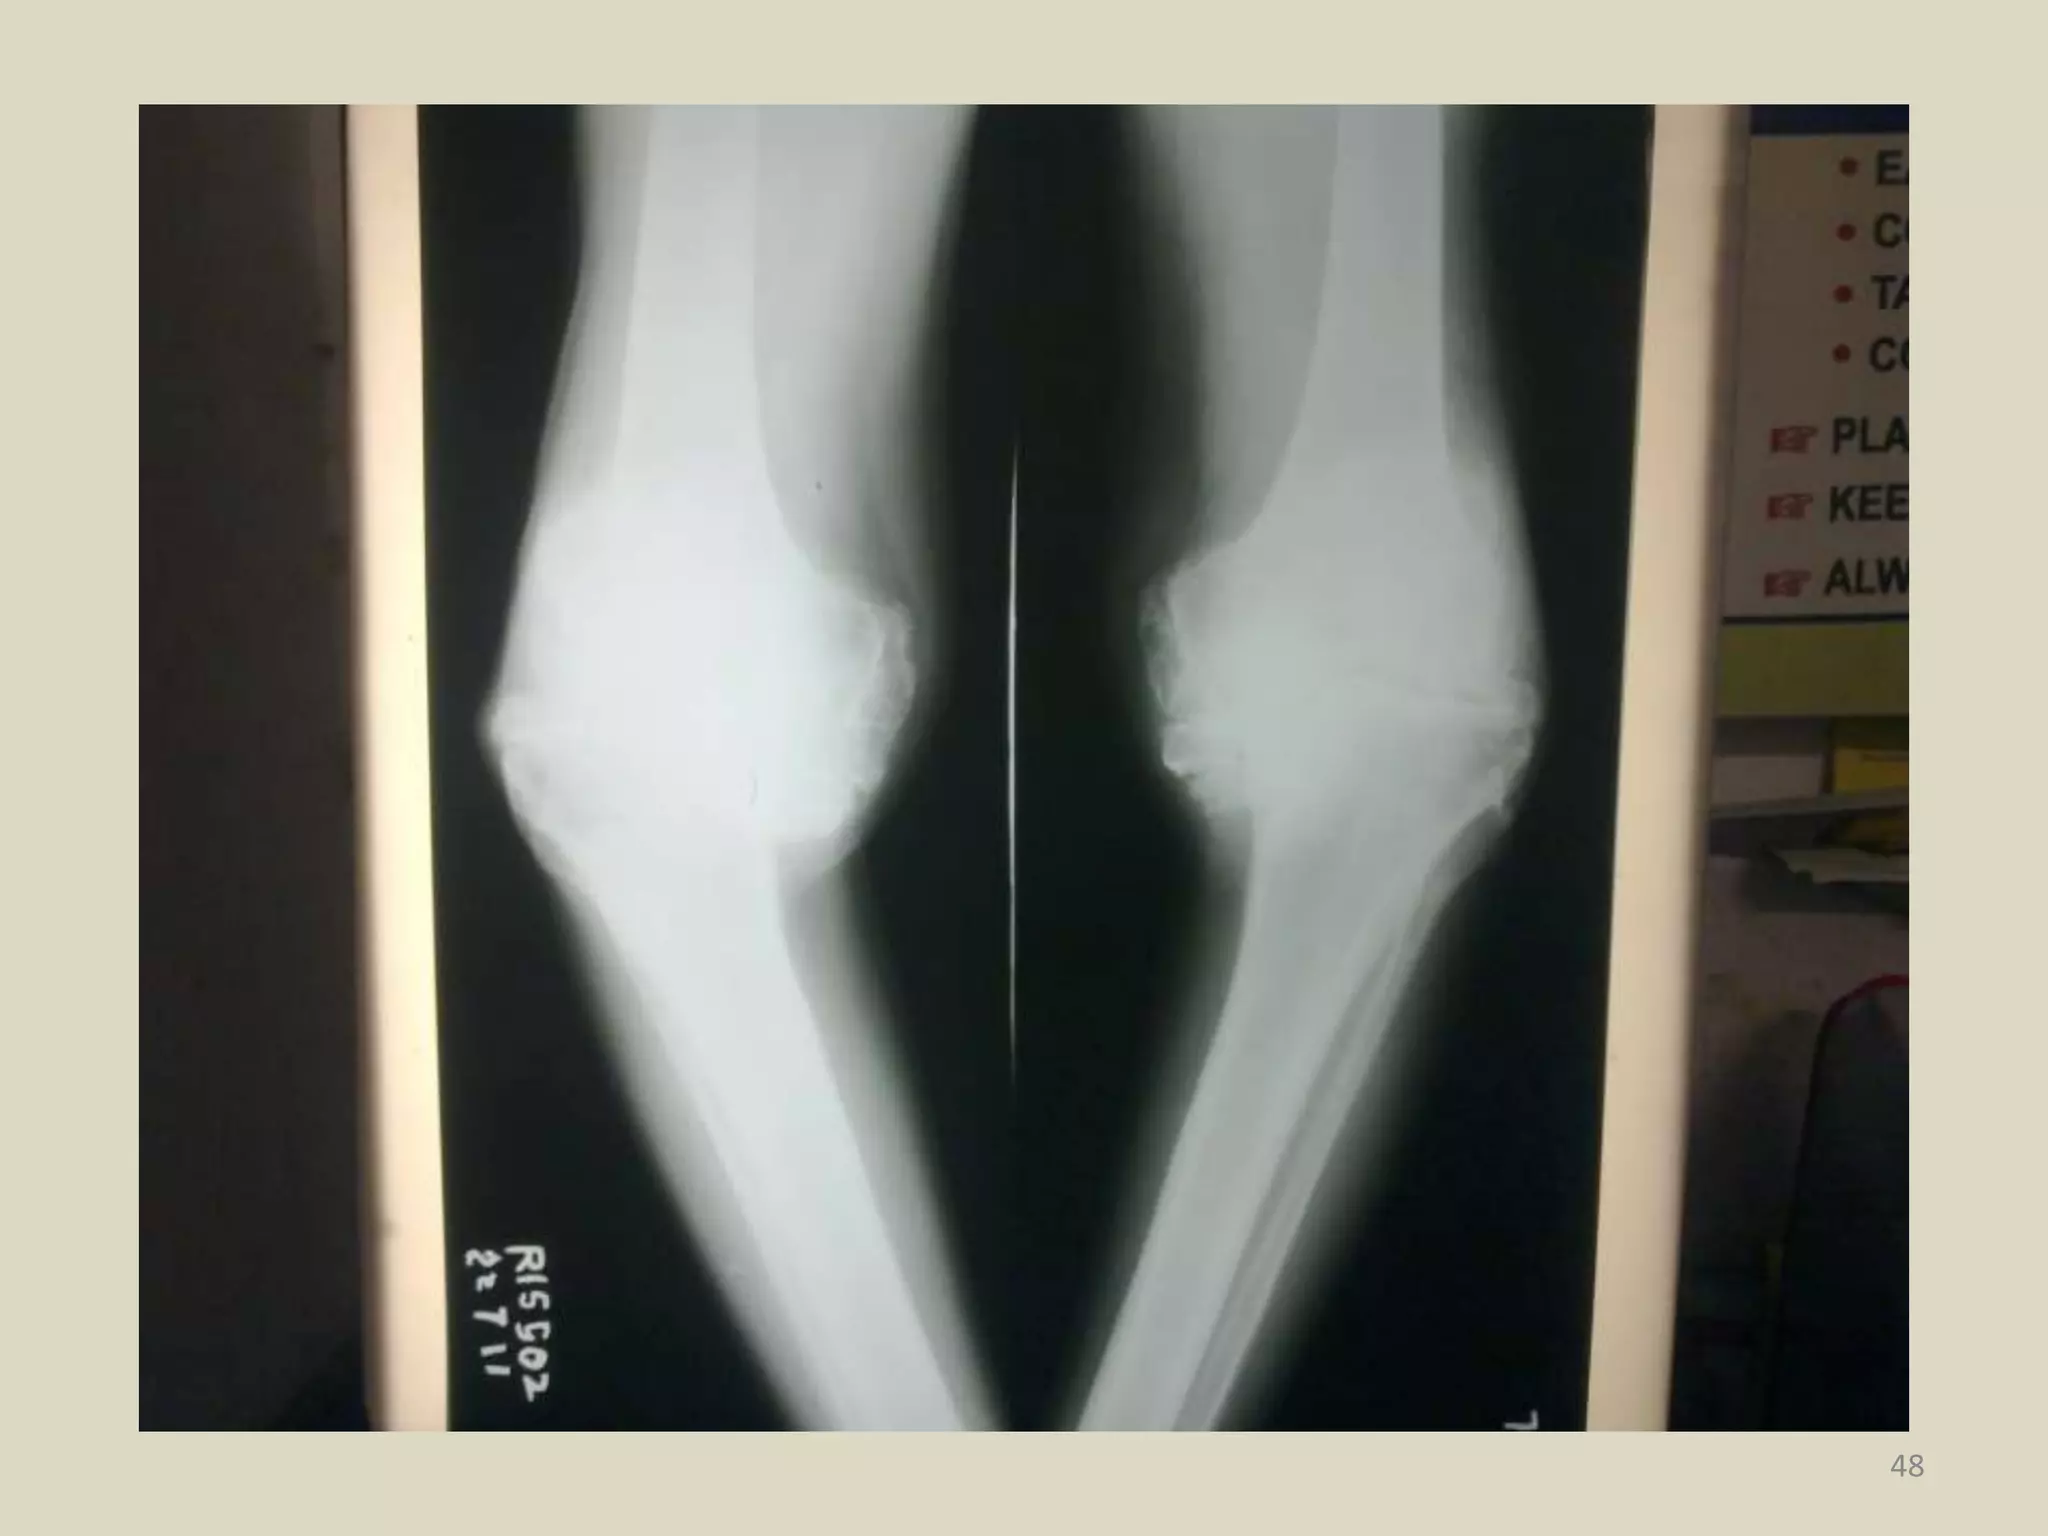

22 Jul 2011

(Ex- Sub) Gurmukh Singh, 65 Yrs

Old case of Hypertension with Type

2 DM on medication for past 15 Yrs

Diagnosed with Osteoarthritis Both

Knees with Varus Deformity.

42 22 Jul 2011 (Ex-Sub) Gurmukh Singh, 65 Yrs Old case of Hypertension with Type 2 DM on medication for past 15 Yrs Diagnosed with Osteoarthritis Both Knees with Varus Deformity.